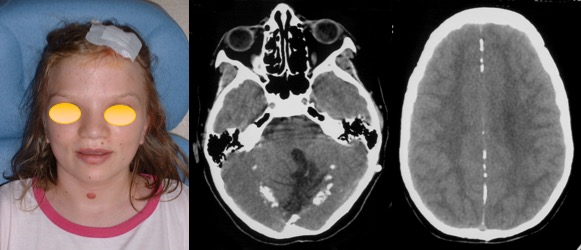

diagnostic

la présentation est souvent aiguë, avec admission en urgence pour hydrocéphalie obstructive (constante dans notre expérience). si on compare les médulloblastomes avec les autres tumeurs de la fosse postérieure, on note que la durée évolutive est plus courte que pour les astrocytomes, et qu’il s’agit d’enfants plus âgés que pour les épendymomes, avec significativement plus de garçons que de filles.

elle peut être très évocatrice, montrant une tumeur spontanément hyperdense en scanner, avec une prise de contraste hétérogène et une hypercellularité bien montrée par la séquence en diffusion.

l’aspect radiologique peut cependant être trompeur.